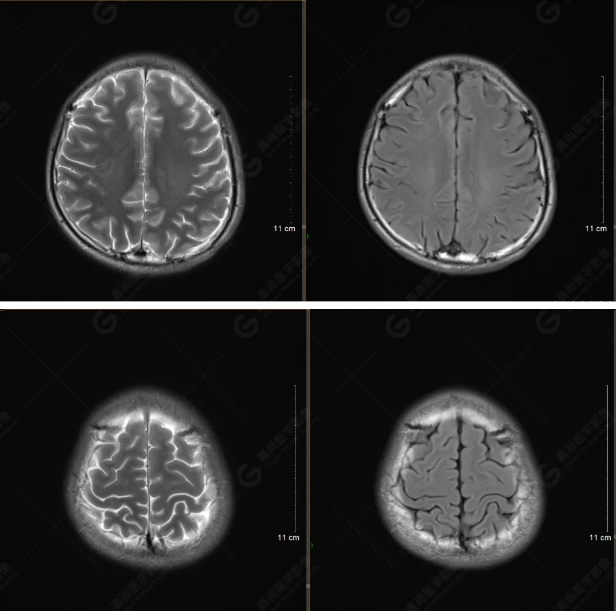

以下是平掃T2WI及FLAIR序列:

雙側(cè)大腦半球?qū)ΨQ,灰白質(zhì)對比正常,顱內(nèi)未見異常信號影。腦室系統(tǒng)未見擴(kuò)大,中線結(jié)構(gòu)居中。腦溝、裂未見增寬。幕下小腦、腦干未見異常。矢狀位示垂體形態(tài)、大小級信號未見異常。所示左側(cè)乳突內(nèi)見多發(fā)短T1長T2信號影。

顱腦MRI平掃未見明顯異常,左側(cè)乳突內(nèi)積血,建議補(bǔ)充SWI檢查。